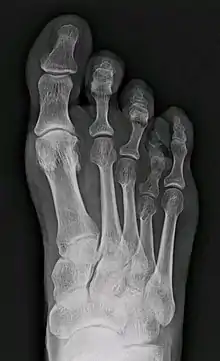

| X-ray of congenital brachymetatarsia involving fourth metatarsal bone | |

It most frequently involves the fourth metatarsal. If it involves the first metatarsal, the condition is known as Morton's syndrome. Treatment is via a number of differing surgical procedures.[3]